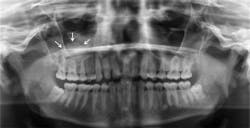

Radiographic distinguishing characteristics: The classic antral pseudocyst presents as a dome-shaped lesion on the maxillary sinus floor. Most have a very faint, opaque appearance on a radiograph. The lesion is usually well delineated (see Figure 1). There is sometimes confusion with the AP and polyps. Polyps are irregular in shape when compared to the AP. The fluid in polyps is in the loose connective tissue of the lamina propria of the lining of the sinonasal tract, and the mucosa is thickened by edema.